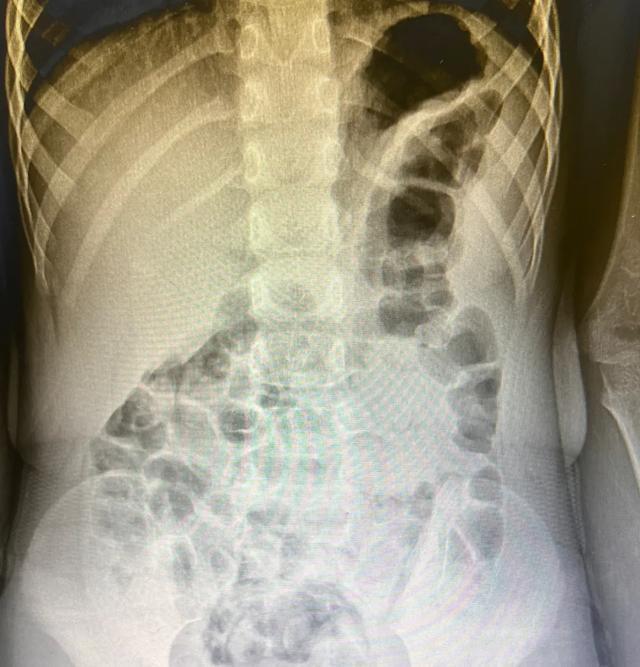

4. 腹部体征:查体时可能触摸到硬便蓄积,尤其在结肠区域。腹部可能波及硬块或可见腹部推广。